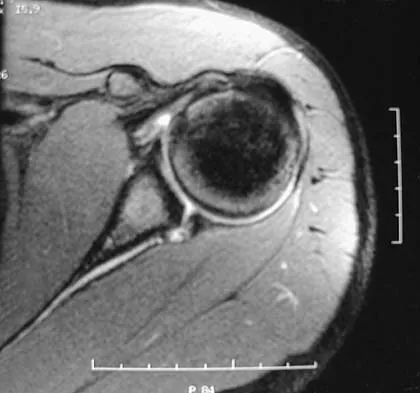

Figures 10a and 10b show the radiographs of a 47-year-old man who reports pain in both shoulders. He has a history of leukemia that was treated with chemotherapy and high-dose cortisone. What is the most reliable treatment option for pain relief in this patient?

Explanation

The radiographs reveal osteonecrosis with collapse. The most reliable and durable treatment for osteonecrosis of the humeral head remains prosthetic shoulder arthroplasty. Osteonecrosis of the humeral head may be seen after the use of steroids, and there is an increasing demand for shoulder arthroplasty in young people because of the use of high-dose steroids in chemotherapy regimes for the treatment of malignant tumors. The indications for most shoulder arthrodeses today include posttraumatic brachial plexus injury, paralytic disorders in infancy, insufficiency of the deltoid muscle and rotator cuff, chronic infection, failed revision arthroplasty, severe refractory instability, and bone deficiency following resection of a tumor in the proximal aspect of the humerus. Clearly, the role of arthroscopy and related minimally invasive techniques in the treatment of humeral head osteonecrosis remains unknown. Hasan SS, Romeo AA: Nontraumatic osteonecrosis of the humeral head. J Shoulder Elbow Surg 2002;11:281-298. Hattrup SJ: Indications, technique, and results of shoulder arthroplasty in osteonecrosis. Orthop Clin North Am 1998;29:445-451.